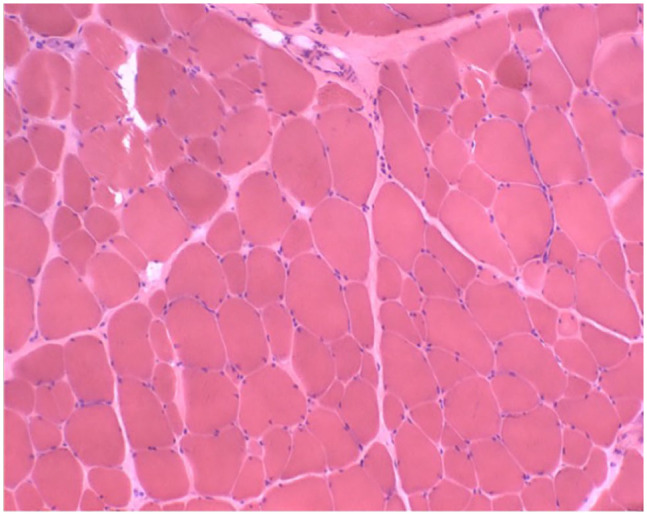

Case summary: A 2-year-old female intact domestic shorthair cat was referred to the neurology service at the Foster Hospital for Small Animals as a result of lifelong weakness, seizure-like episodes after excitement, muscle spasms, stiffness of the limbs and shortness of breath. A diagnosis of myotonia congenita (MC) was made based on compatible history, clinical signs and electromyography findings, and excluding other causes of muscle weakness using muscle biopsy, baseline bloodwork and echocardiography. Initial treatment with procainamide had overall low efficacy. The cat was then switched to carbamazepine, which provided long-term improvement in clinical signs at a dosage of 7.4 mg/kg PO q12h with no observed clinical side effects.

Relevance and novel information: To date, there is only a single case report describing the successful treatment of MC in cats, and no report describing the use of carbamazepine to treat this condition in this species. This anti-convulsant medication was shown to be anecdotally effective in the case reported. Further research is needed to categorize the metabolism, pharmacokinetics, tolerance, dose range and efficacy of carbamazepine in cats with and without MC.